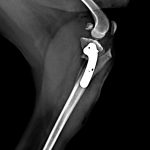

ビーグル(15kg)の左前十字靭帯断裂に対するTPLO術(脛骨高平部水平化骨切術)☑